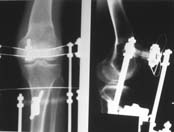

Пациент В. 53 лет, травма в феврале 2009. ДЗ. Открытый оскольчатый перелом нижней трети голени. При боли поступлении выполено ПХО, аппарат Илизарова. В последующем проводили ВХО, резекция костных отломков, укорочение 6 см, рана зажила. Была выполнена остеотомия большеберцовой кости в проксимальном отделе, резекция. Производилось тракция. На последних рентгенограммах выявлено, что одновременно с "выращиванием" регенерата произошло низведение надколенника на длину выращенного регенерата. Клинически: активное разгибание сохранено, объем движений в колене 180-110 градусов. Черными стрелками обозначен верхний край надколенника с одной и с другой стороны. Красная стрелка обозначает пальпируемую связку надколенника. Причина - остеотомия выше места прикрепления связки надколенника. Вопрос: была ли у кого подобная ситуация? Что делать? При первом обдумывании приходит решение: отсечение места прикрепления связки надколенника с костным блоком, перемещение на "правильное" место, укорочение сухожилия четырехглавой мышцы.

К сожалению, подобное осложнение "нет-нет да и возникает" при удлинении, коррекции деформации голени. В англоязычной литературе оно описано как "patella baja". Один из вариантов лечения - проксимальное перемещение надколенника приемами чрескостного остеосинтеза.

По-моему, надколенник низвелся на величину, гораздо меньшую удлинению.

Я бы уменьшил диастаз между фрагментами сантиметра на два. Судя по снимкам, регенерат это может позволить.